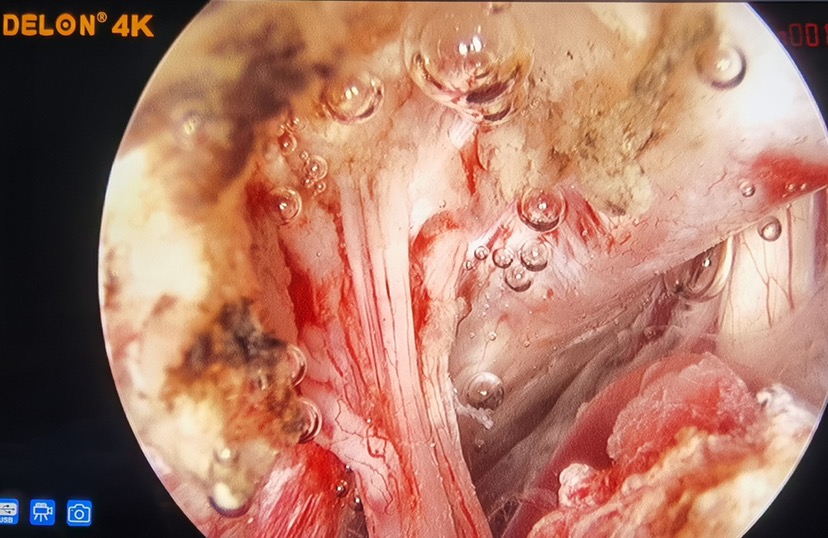

手术采用左侧远外侧入路,使用纯内镜手术,内镜采用国产德龙4K纯高清内镜摄像系统,发现左侧第Ⅸ、第Ⅹ和第Ⅺ颅神经穿过颈静脉孔处肿瘤。

术中显示肿瘤质地较硬,直径约1cm,包绕左侧第Ⅸ、第Ⅹ和第Ⅺ颅神经并与硬脑膜粘连紧密。使用精细磨钻磨除颈静脉孔区部分骨质,充分暴露肿瘤。在电生理监测和德龙4K超高清内镜系统显示下完全切除肿瘤,保留神经,未出现大出血。